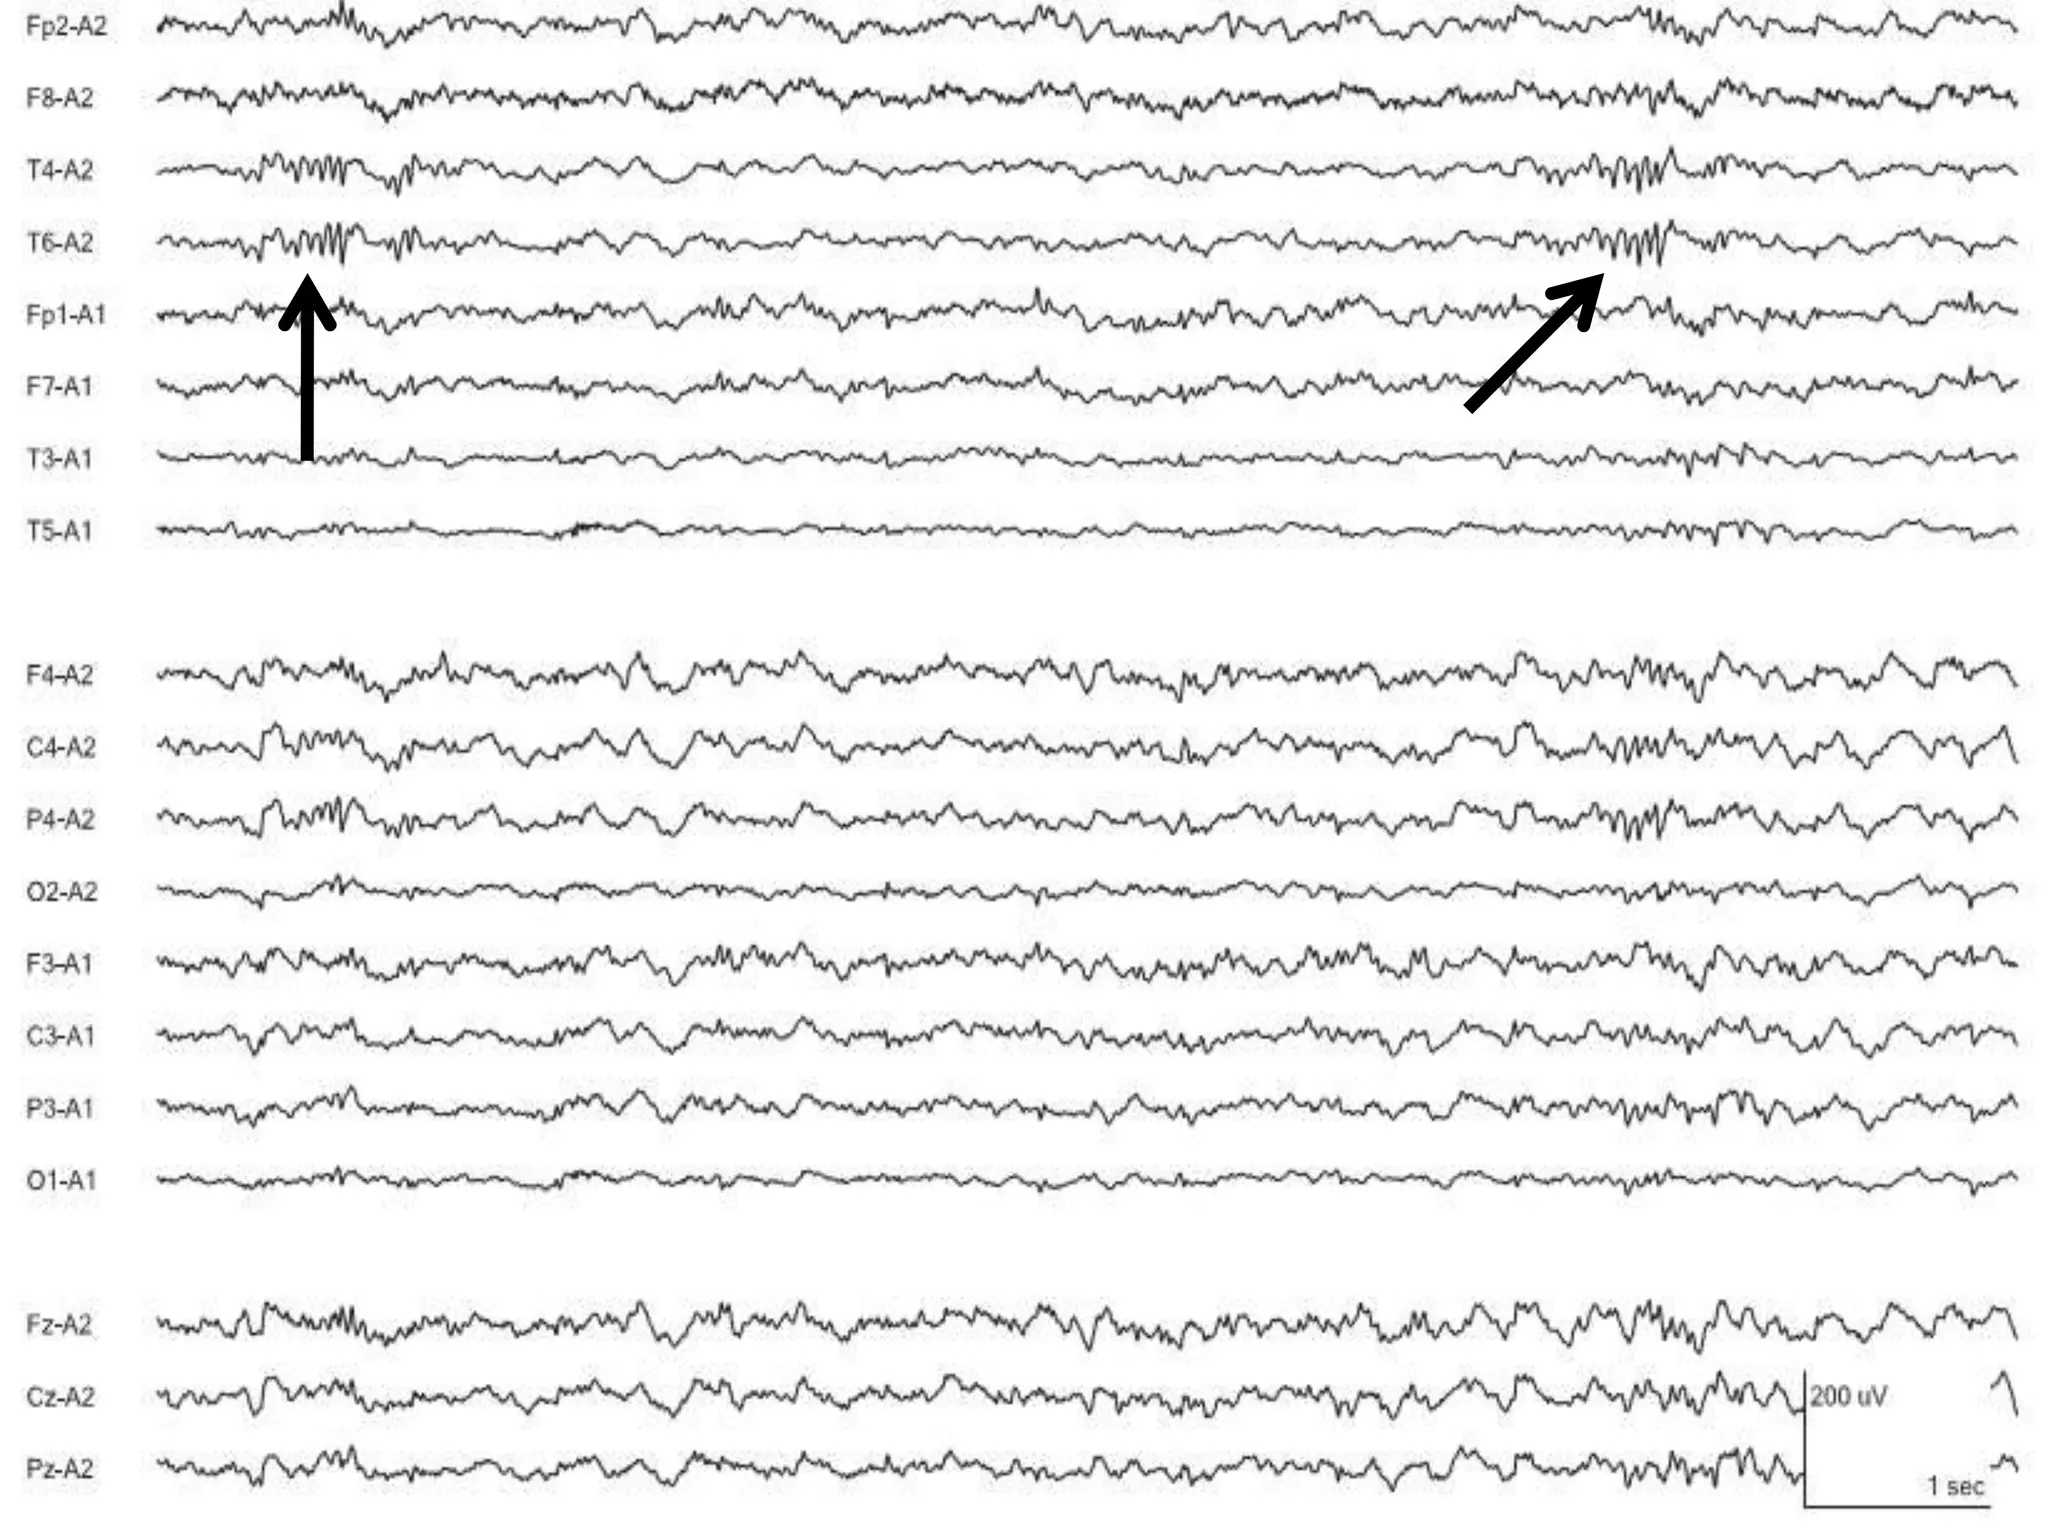

Wicket waves

• Short runs of 6-11Hz spikes, sometimes single spike

– usually within alpha frequency range

• Monophasic arciform waveforms (60-200uV)

• Anterior or mid-temporal region

– Usually unilaterally,shifting emphasis between sides

• Sharp monophasic, no slow wave

• Present in relaxed wakefulness, drowsiness, light sleep

• Usually in middle and late adulthood

• Clinical significance: analogue of the auditory alpha rhythm

– May decrease with auditory stimulation

– Not associated with epilepsy

Wicket waves • Shortruns of 6-11Hz spikes, sometimes single spike – usually within alpha frequency range • Monophasic arciform waveforms (60-200uV) • Anterior or mid-temporal region – Usually unilaterally,shifting emphasis between sides • Sharp monophasic, no slow wave • Present in relaxed wakefulness, drowsiness, light sleep • Usually in middle and late adulthood • Clinical significance: analogue of the auditory alpha rhythm – May decrease with auditory stimulation – Not associated with epilepsy